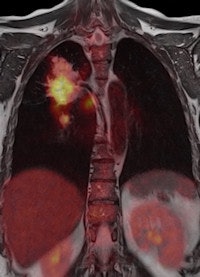

When the doors of the ECR 2011 technical exhibition burst opened this morning, a host of surprises and innovations awaited congress attendees. Arguably the biggest highlight of all is the first PET/MR system ever displayed at the Austria Center, and it looks certain to attract massive attention and interest over the next four days.

A combination of MRI and PET has long been considered as the logical next step in the evolution of imaging modalities, but industry has struggled to deal with the formidable technical challenges of achieving a happy marriage between the two approaches, notably the difficulties of developing a PET detector capable of coping with the powerful static and dynamic magnetic fields generated by the MR coils. GE Healthcare made the first important move in developing the software needed to integrate data acquired through sequential scans made using the two modalities. Then Philips brought the two main items of hardware alongside each other, linked by a revolving table for easy patient transfer, and the company installed the first European system in a hospital in Geneva in April 2010. Now Siemens' engineers have successfully merged the two modalities in a single unit, dubbed the Biograph mMR, which the vendor plans to launch commercially later this year.

Dr. Alexander Drzezga, from the university's department of nuclear medicine, has been responsible for setting up the system, which was delivered in November 2010. It is currently being used to scan up to five patients a day, but that number is likely to grow as the Munich team explores the limits of the unit's clinical potential. "Many neurological conditions are suitable for evaluation with PET/MR, including neurodegenerative disorders, dementia, epilepsy, and brain tumors. With regard to evaluation of the cardiac system, combined imaging of PET and MR may also show diagnostic advantages, while inflammation and vascular conditions are also areas of interest," he explained.

Drzezga believes that combining the two modalities offers a number of clinical advantages, not least in eliminating the need for separate diagnostic examinations. Furthermore, the exact anatomical registration of structural and functional/molecular information may improve allocation of suspect findings and improve image quality, for example by motion correction of regions of the body that do not remain rigid during examination. The Munich team will also be exploring how the performance of PET/MR compares with that of PET/CT. There is some evidence that the superior soft-tissue contrast achievable with the newer system will offer significant benefits, even before physicians consider the safety issues involved with any radiation-based imaging technology such as PET/CT, Drzezga suggested.

The Biograph mMR is based on the Verio 3-tesla MR system with a 70-cm bore that provides enough space to position the PET detector ring and its solid-state photodiodes. In getting the two modalities to work alongside each other, the hybrid molecular MR system can scan the whole body in as little as 30 minutes, compared with an hour or more needed for sequential examinations. The machine also incorporates Siemens' TIM (total imaging matrix) technology, which seamlessly integrates multiple coil elements and radiofrequency (RF) channels and can reduce examination times by up to 50%, according to the vendor.